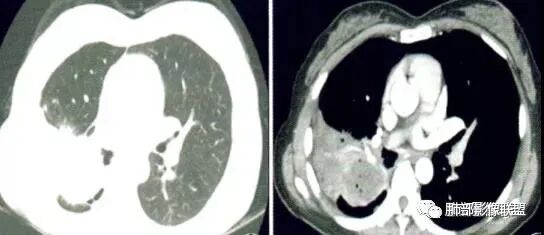

右上叶尖段带状实变影

外围大、内带小,宽基底与胸膜相连,附近卫星灶

支气管进入病灶内,广泛胸膜增厚

支气管粘液栓

血管走形自然

实变区强化较均匀,明显强化

边缘平直为主

支气管堵了,但是远端粘液栓:是粘液栓堵塞?还是狭窄或堵塞后继发粘液栓?

病灶是支气管腔内堵塞导致远端实变、不张?还是外围病灶融合、实变影响近端支气管?

整体考虑肿块应该不支持,因为支气管、血管走形还算自然,只是收缩在一起,如果肿块走形不会这么自然,会推移、变形,侵犯

现有的图显示近端支气管还是连续的,只是远端扩张,腔内粘液栓,其实还应当看重建的支气管连续的图,与近端含气部分的连续